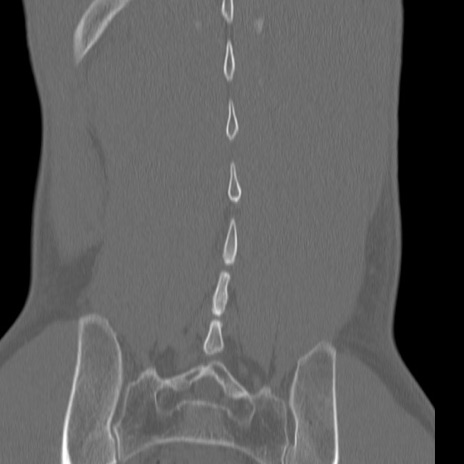

症例3 腰椎CT(冠状断像)

腰椎CT

3D再構成